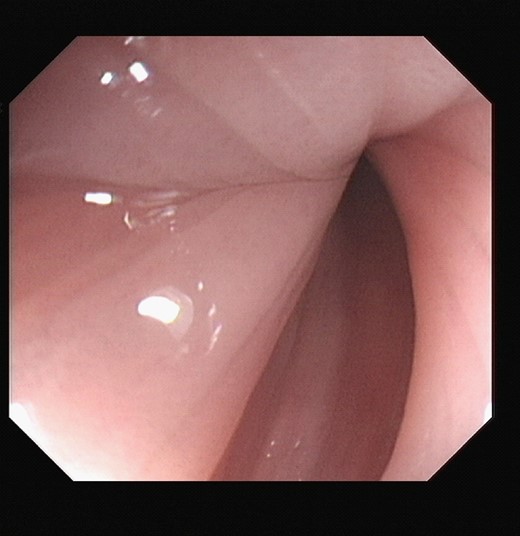

At sigmoidoscopy, the volvulus was successfully decompressed. The mucosal lining was pink and healthy in appearance, Fig. 4. Mr. X improved following this intervention.

Unfortunately on the fifth day of Mr. X’s admission, he became acutely unwell with left iliac fossa pain and vomiting. Repeat sigmoidoscopy revealed a blue mucosa which appeared ischaemic with no visible peristalsis. Attempted decompression was unsuccessful, Fig. 5.